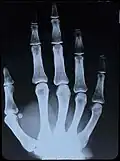

Original: X-Ray image of right Hand;

1st. order equidensities after pseudo-solarization of original -

colored 1st. order equidensity-series using pseudo-solarization, B&W copies chromogenic developed